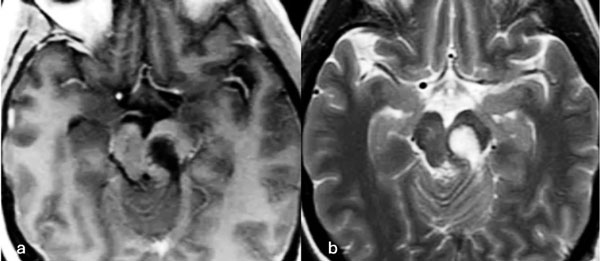

Figura 2. RM postquirúrgica de encéfalo. Se evidencia una exéresis completa, sin lesión de estructuras adyacentes. A) Imagen ponderada en T1 posterior a la administración de gadolinio, corte axial. B) Imagen ponderada en T2, corte axial.

Caso 1: cavernoma mesencefálico

Una mujer de 35 años debutó con un cuadro de cefalea asociada a diplopía por parálisis del tercer par craneal izquierdo y hemihipoestesia del hemicuerpo derecho. La RM de encéfalo evidenció una malformación cavernomatosa tegmental izquierda con signos de sangrado reciente. Un año después del sangrado, la paciente fue sometida a una exéresis de la lesión mediante un abordaje suboccipital lateral y supracerebeloso infratentorial izquierdo (Figura 1), logrando una exéresis completa de la malformación (Figura 2). Después del procedimiento, la paciente no presentó nuevos déficits agregados.